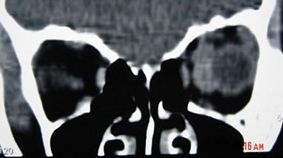

眼眶血管瘤(如图)的常见表现( )

A:视力障碍

B:疼痛

C:眼球运动障碍

D:突眼

E:搏动感